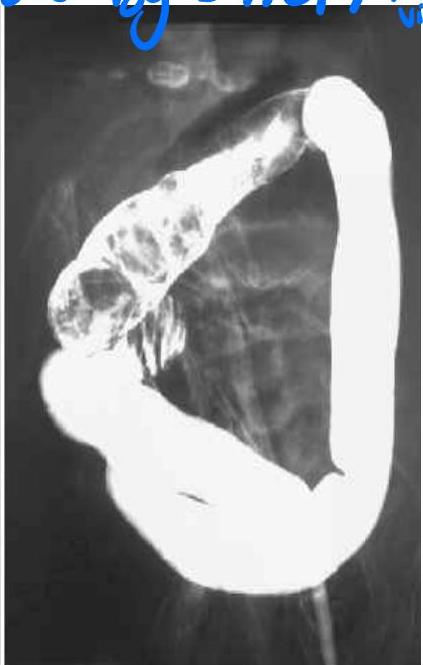

Corrosive Poisoning / Esophageal Stricture

Scenario: 3 year old poisoned at home with severe acute injury and long-term complications.

Poison type? Corrosive (bleach, disinfectants, detergents, cleaning agents).

Barium swallow finding? Esophageal stricture.